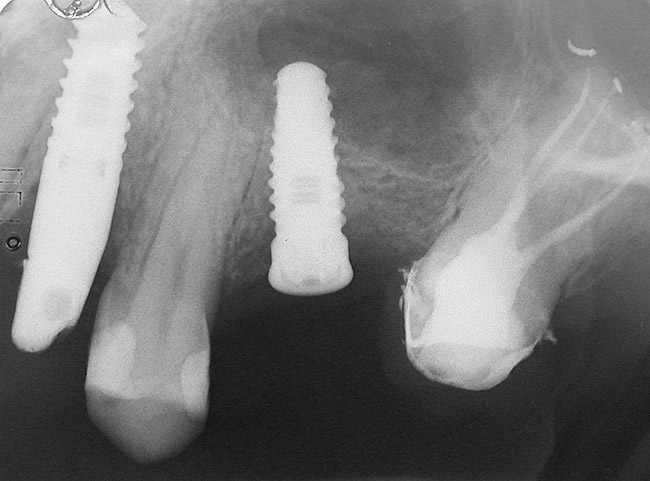

A full-thickness mucoperiosteal flap was raised, and alternating osteotomes were used to prepare the implant site. After achieving a length of 7 mm (Figure 7A and Figure 7B), heterologous bone graft was implanted and the osteotome sequence was repeated. The implant showed primary stability.

Second-stage surgery was performed after 4 months (Figure 8); healing abutments were placed and the soft tissue was allowed to heal for 5 more weeks. Then, splinted porcelain-fused-metal (PFM) crowns supported by custom gold abutments were delivered (Figure 9 and Figure 10).

Figure 8  At 4 months after treatment, the radiograph revealed the presence of a bone layer surrounding the implant.

Figure 8